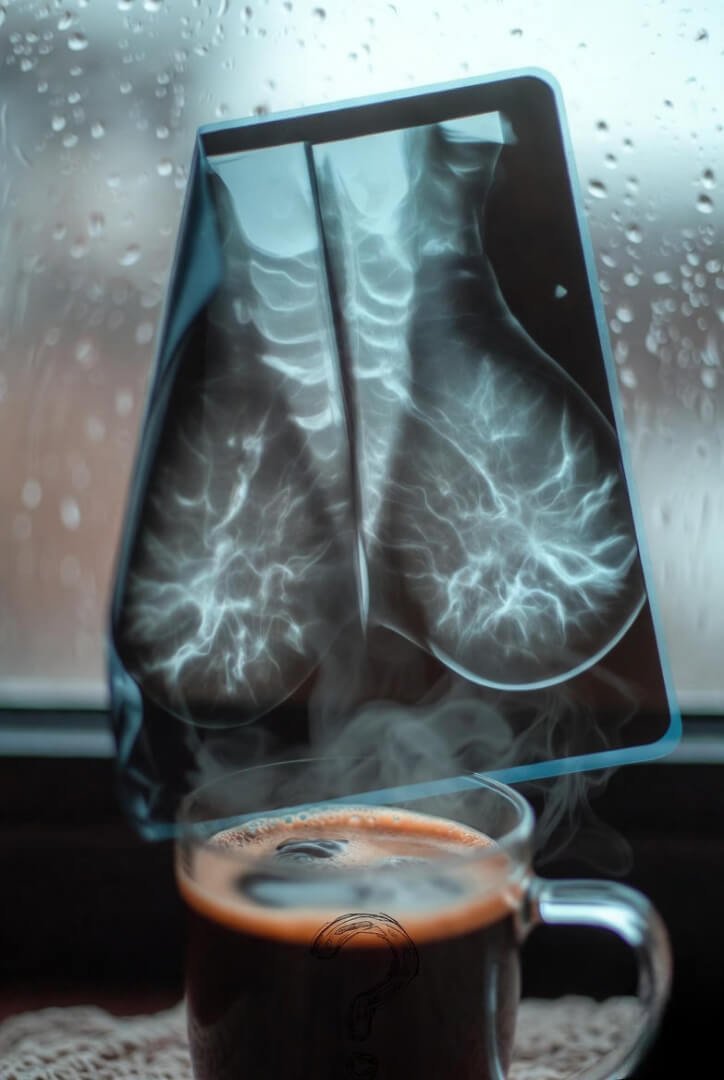

Couple weeks later I’m in a cath lab getting stents like it’s no big deal. Turns out there was some pretty ugly blockage going on. Caught it before the widow-maker version showed up, thank god (and thank my wife mostly).